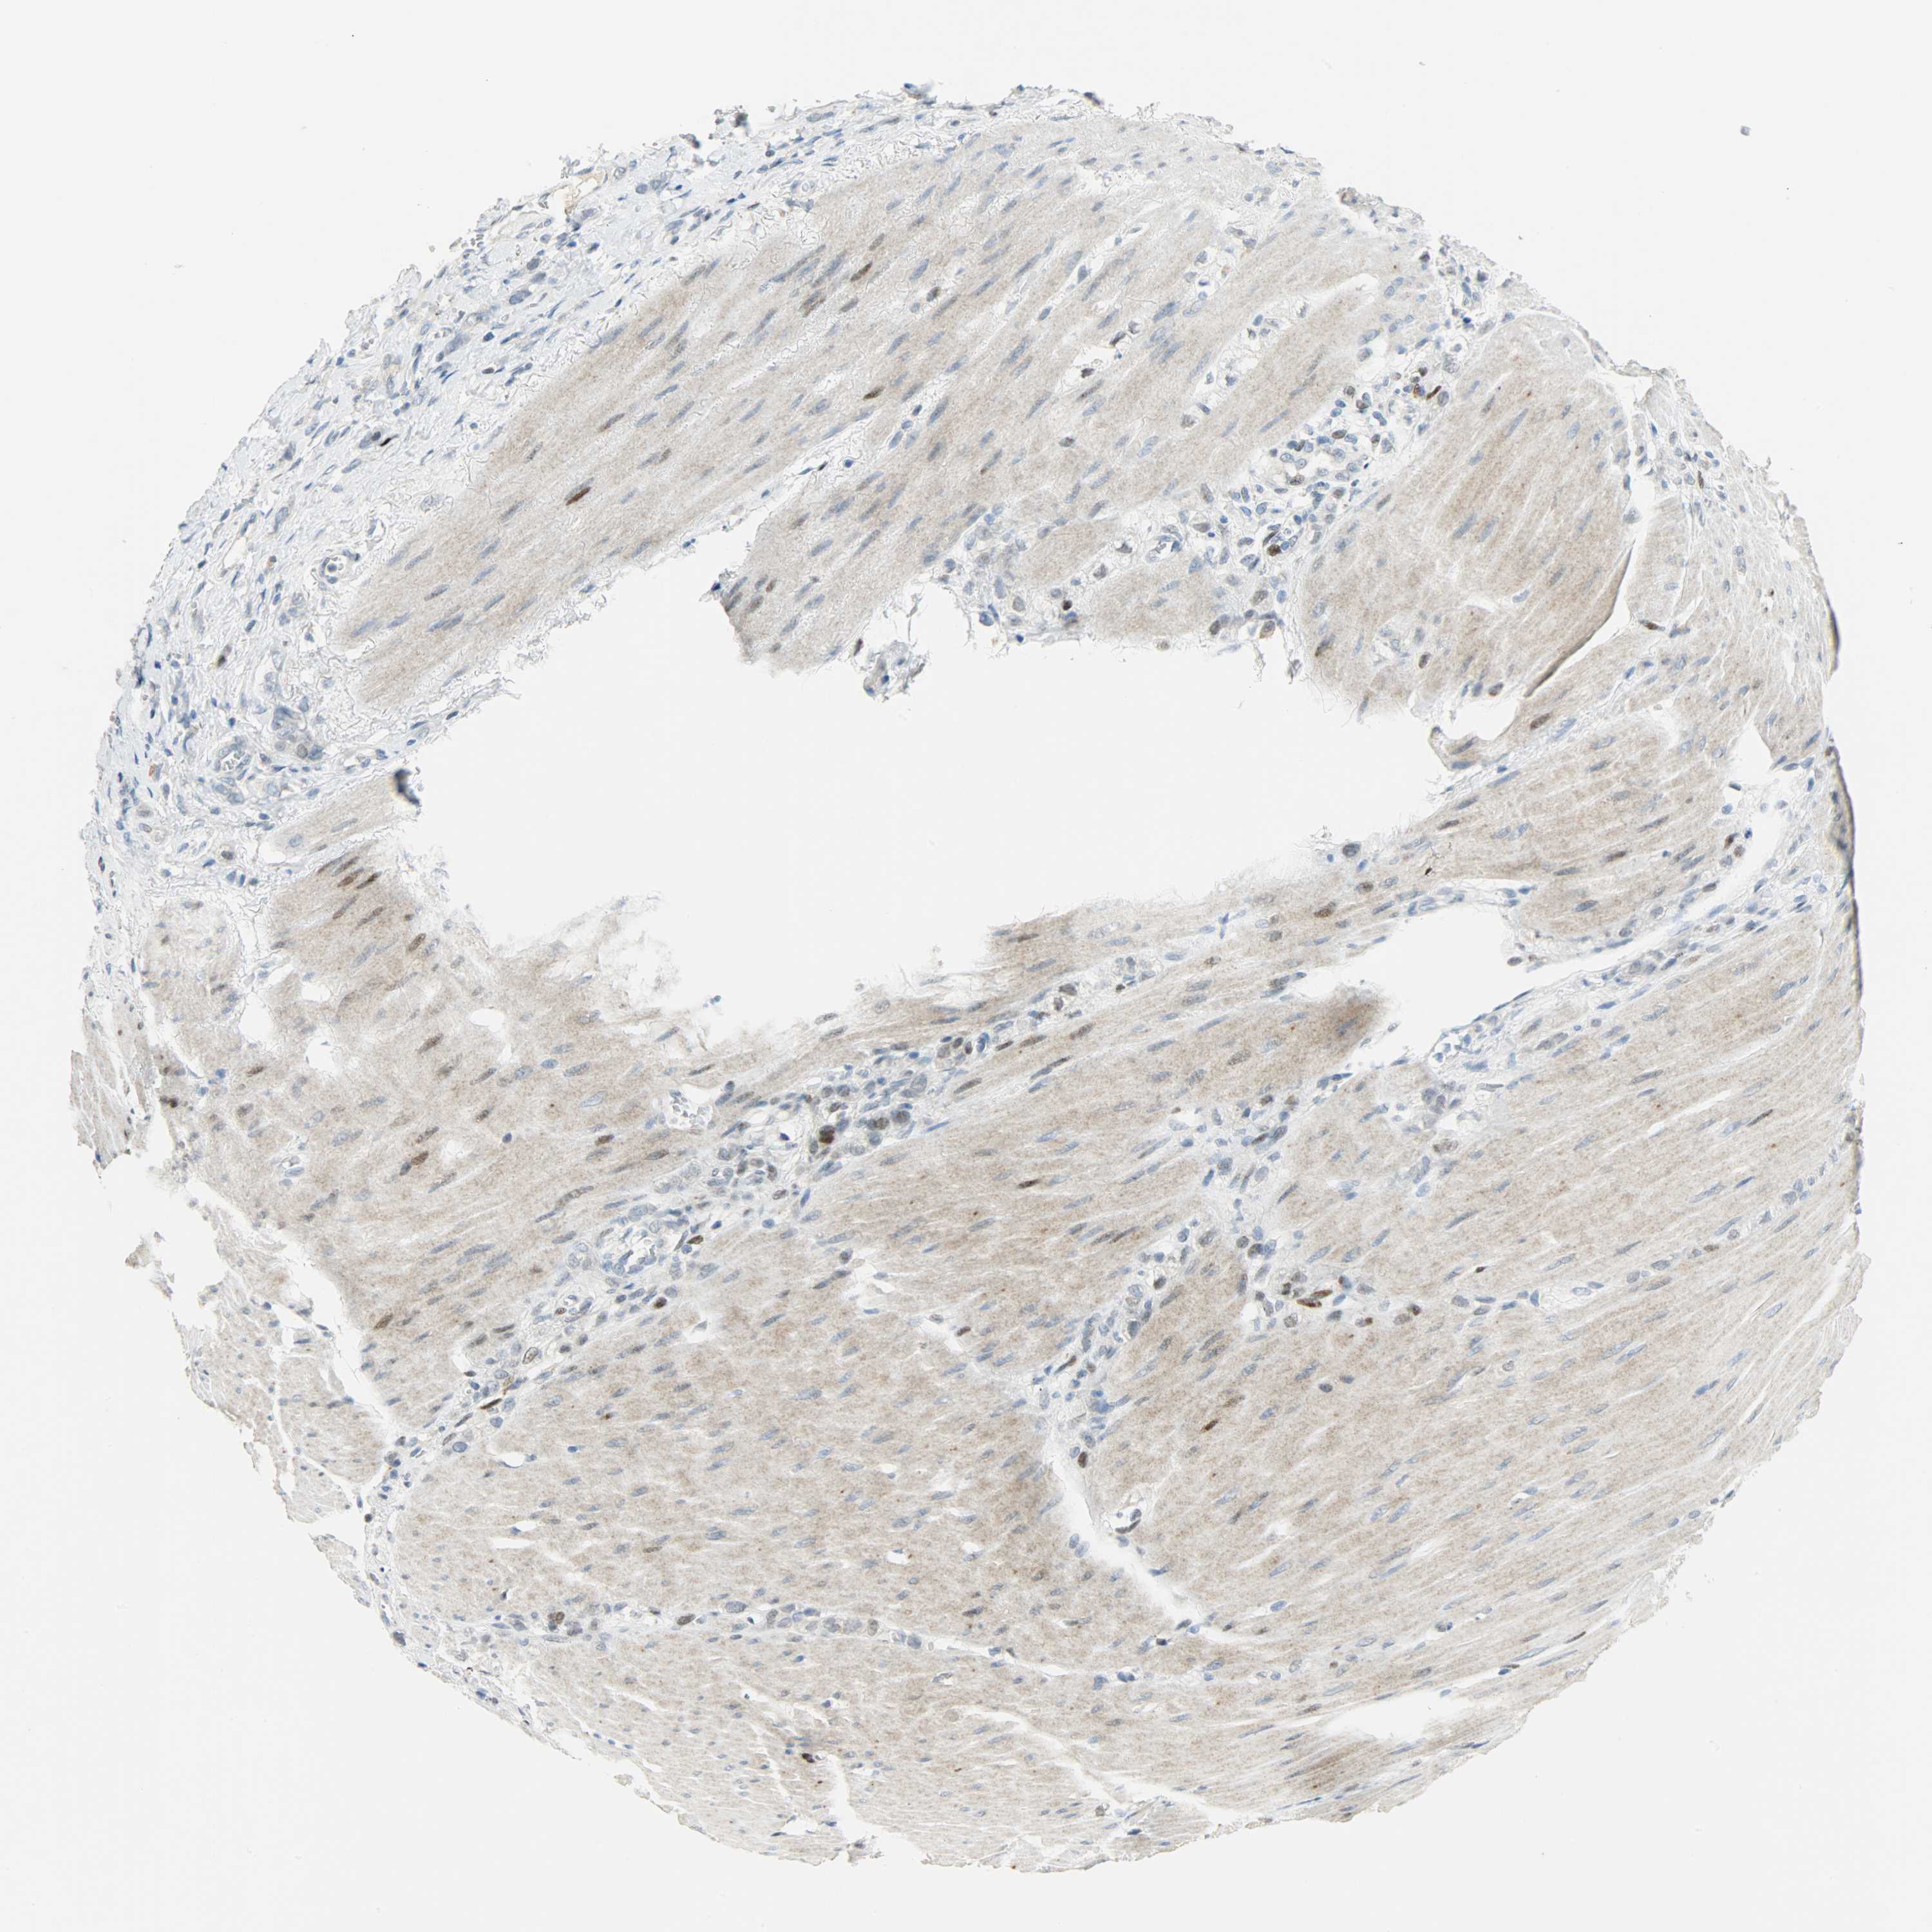

STOMACH CANCER - Protein expressioni

A mouse-over function shows sample information and annotation data. Click on an image to view it in a full screen mode. Samples can be filtered based on level of antibody staining by selecting one or several of the following categories: high, medium, low and not detected. The assay and annotation is described here.

Antibody stainingi

Antibody staining in the annotated cell types in the current human tissue is reported as not detected, low, medium, or high, based on conventional immunohistochemistry profiling in selected tissues. This score is based on the combination of the staining intensity and fraction of stained cells.

Each image is clickable and will lead to virtual microscopy that enables deeper exploration of all samples and also displays staining intensity scores, fraction scores and subcellular localization as well as patient and tissue information for each sample.

Antibody HPA019149

Antibody CAB004464

Staining

High

Medium

Low

Not detected

Intensity

Strong

Moderate

Weak

Negative

Quantity

>75%

75%-25%

<25%

None

Location

Nuclear

Cytoplasmic/membranous

Cytoplasmic/membranous,nuclear

Adenocarcinoma, NOS

Adenocarcinoma, High grade